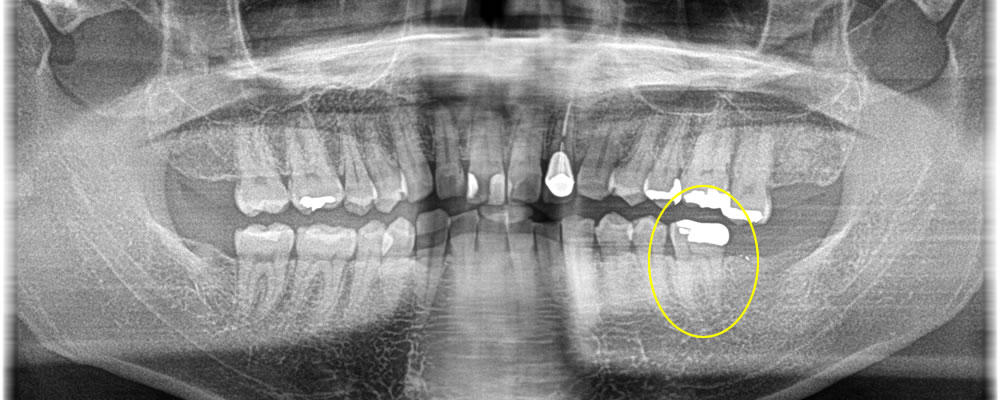

こちらの患者さまは、左下一番奥の歯に痛みがあるとのことで来院されました。

もともと入っていた銀歯が古くなっており、除去したところ歯根に破折線が確認できたため、保存不可能と判断しました。患者さまと相談し、破折した歯を抜歯後にインプラントで治療する計画を立てました。